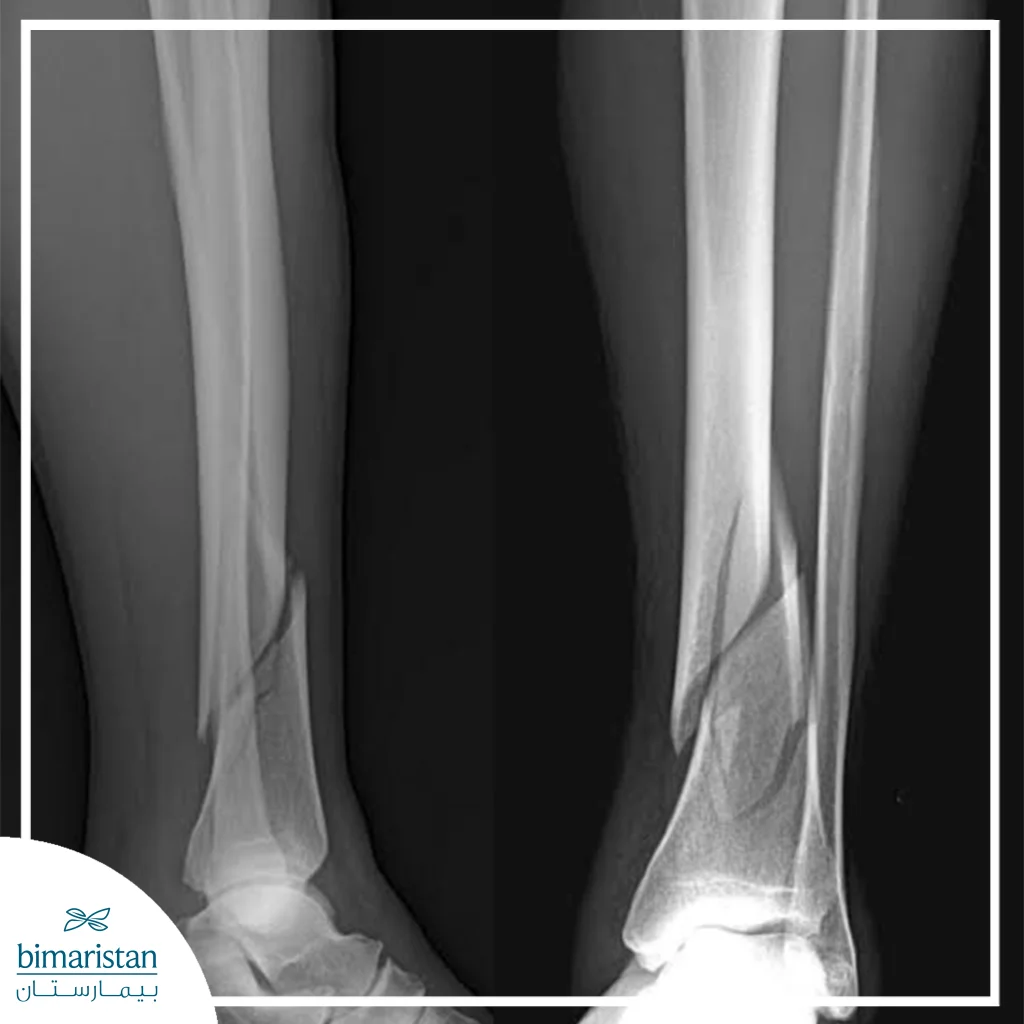

الأشعة السينية

تُعد الأشعة السينية الطريقة الأساسية لتحديد موقع الكسر وطبيعته، توفر صوراً ثنائية الأبعاد للعظام، تساعد الأطباء على معرفة درجة انزياح القطع العظمية، وجود كسور مفتوحة أو مغلقة، ومدى تأثر المفصل القريب. تُستخدم الأشعة السينية قبل العلاج وبعده لمراقبة تقدم الالتئام وضمان ثبات العظم أثناء العلاج التحفظي أو بعد الجراحة.